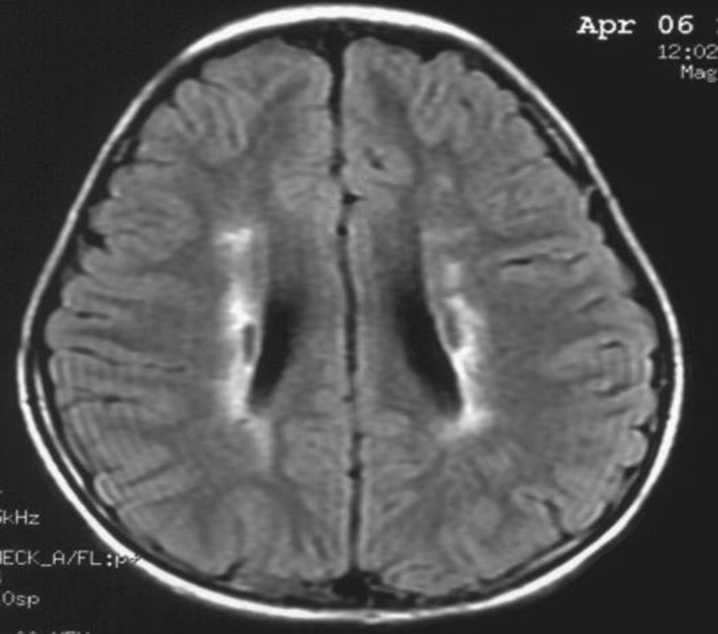

患者:林某某性別:男年齡:8 歲基本情況:出生后3個月臨床和頭部CT檢查診斷為腦癱。8年來病人曾在全國各地接受各種中西醫(yī)治療,病人入院時確診為痙攣性腦癱。治療時間:2005年7月接受干細胞移植手術(shù)。

治療前情況:全身僵硬,尖足,交叉,雙手后背,頸部歪斜。不能獨坐、獨站、不能行走,雙手不能持物。言語含糊,面部僵硬。

治療后情況:全身僵硬緩解,尖足和交叉消失,雙手后背緩解,頸部歪斜消失。可以獨坐一個小時,雙手持物好。言語清晰,面部表情自如。